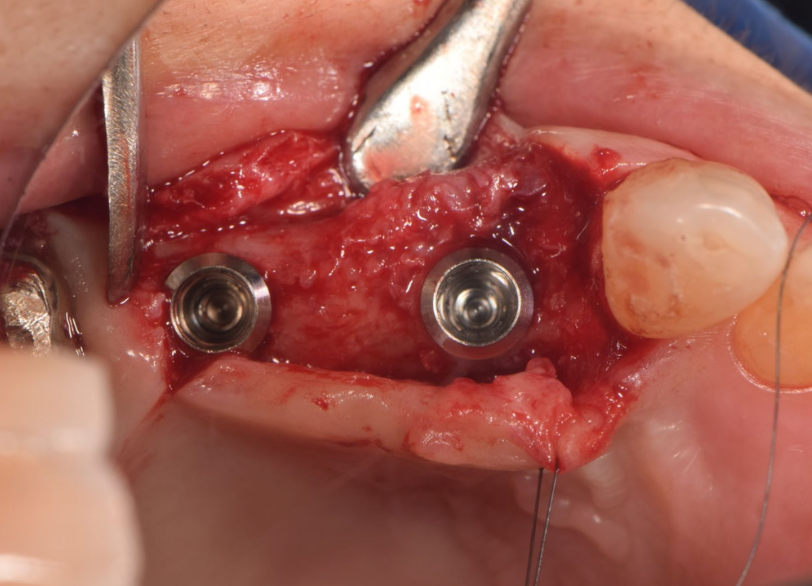

③インプラントを埋入し仮歯装着

顎堤の吸収がなくインプラントを行うにあたり十分な骨が得られた

| 処置内容 (または主訴) | ①義歯 ②顕微鏡を用いた感染根管治療 ③インプラント治療 ④抜歯→骨造成→インプラント ⑤インプラント治療 ⑥セラミックによる被せ物の修復 ⑦セラミックによる被せ物の修復 |